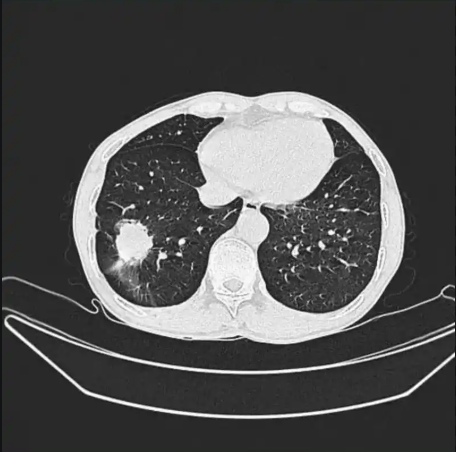

入院后,查胸部增强ct提示典型的蝴蝶症

前一天胸片只提示双肺纹理增多,今天住院查肺ct提示重症肺炎,左肺肺实